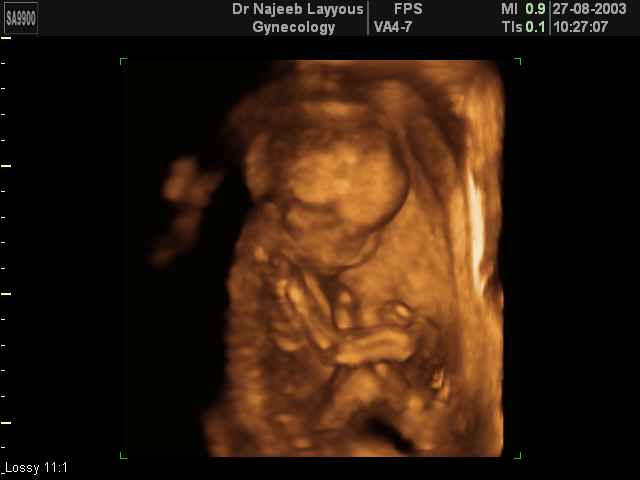

- تصرفات الجنين داخل الرحم

- صور لتصرفات الجنين داخل الرحم

صور لتصرفات الجنين داخل الرحم بجهاز الالتراساوند ثلاثي الأبعاد | الدكتور نجيب ليوس